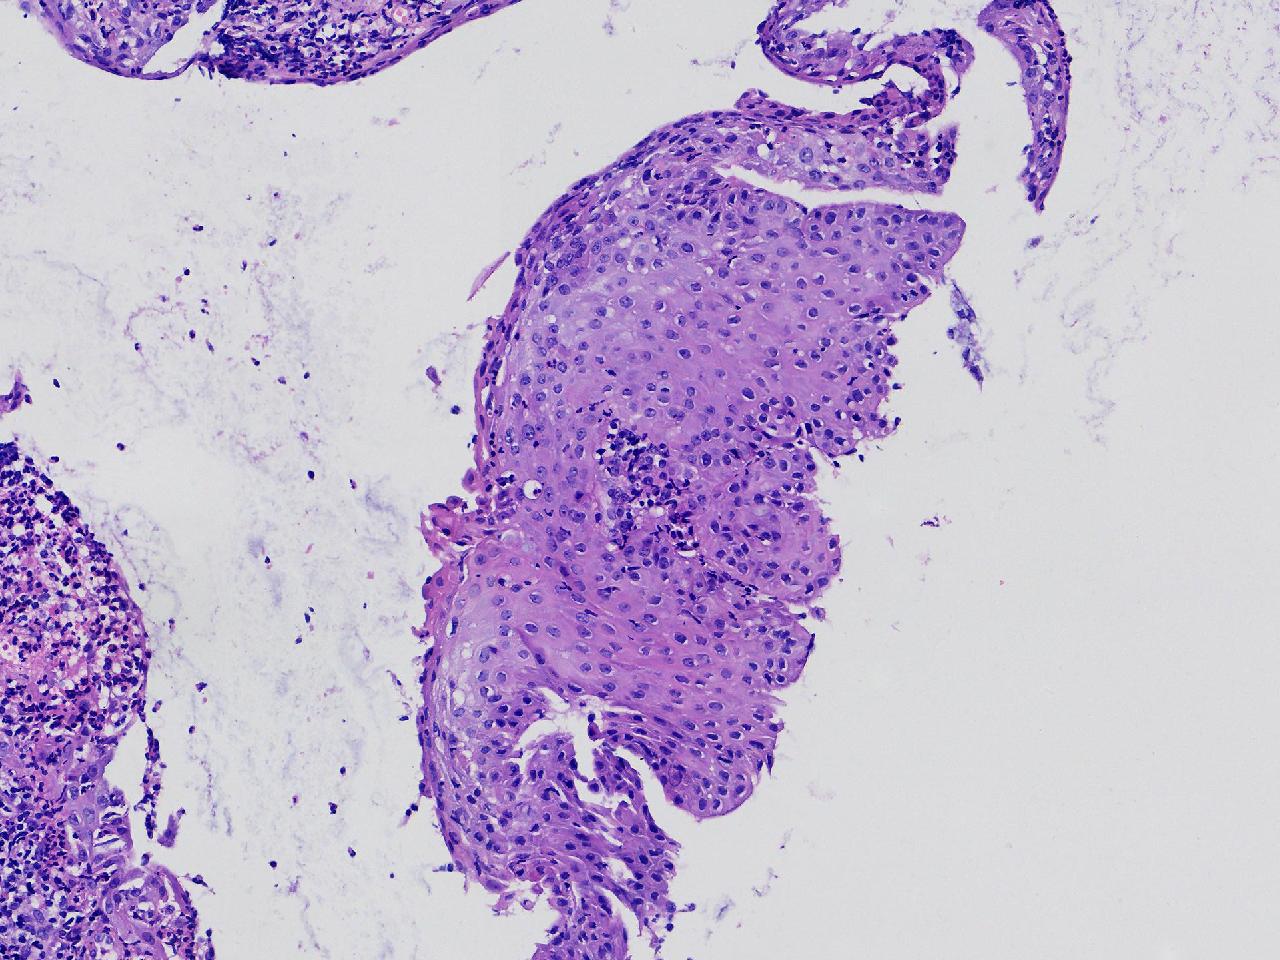

宫颈活检,有没有CIN?

女

36岁

宫颈病变

TCT示:ASC-US,HPV不详。

宫颈活检

图1

慢性宫颈炎伴腺上皮鳞化。

(宫颈活检组织) 慢性炎,储备细胞增生伴鳞化。